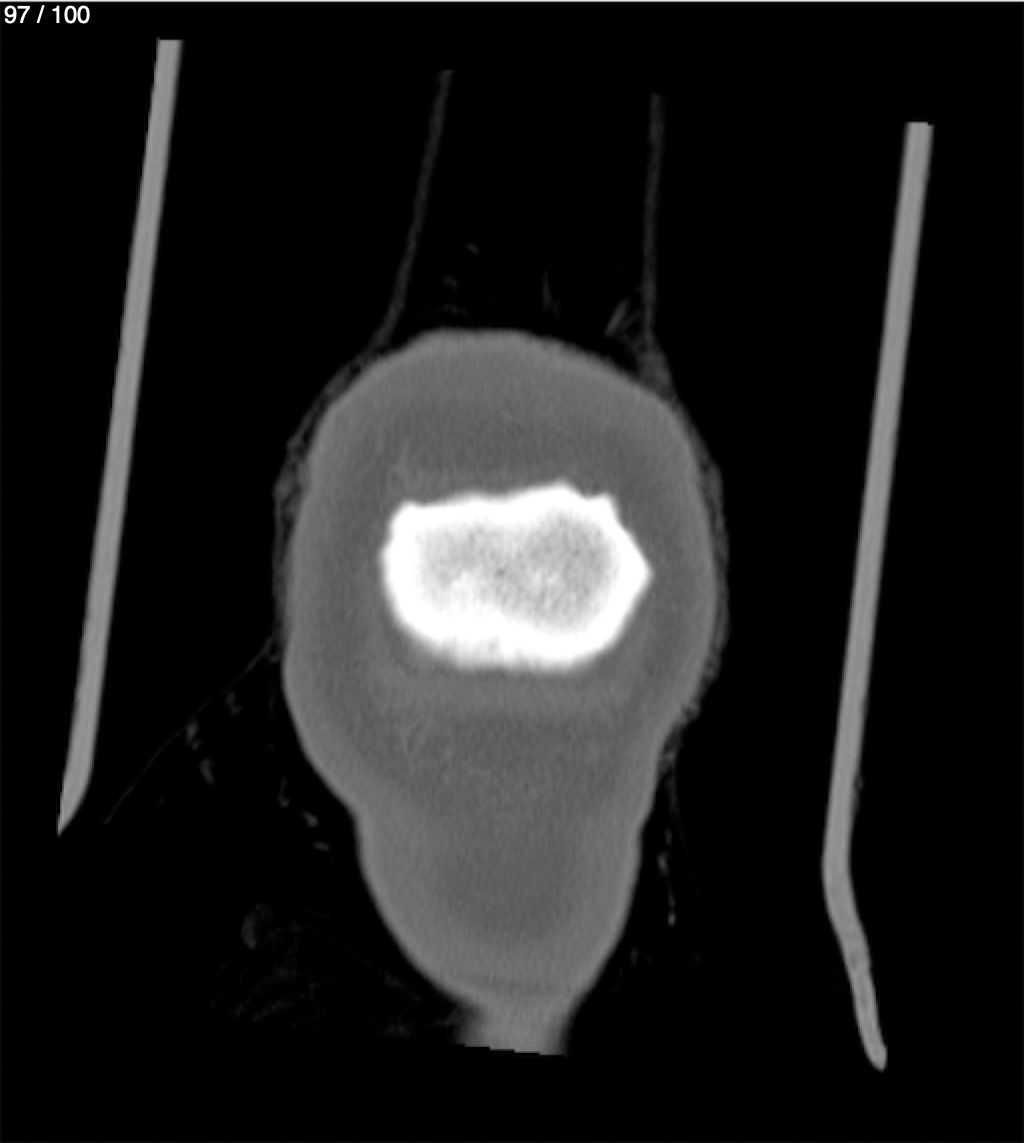

Reybet Garcia Fuentes 30A - T.C Craneo